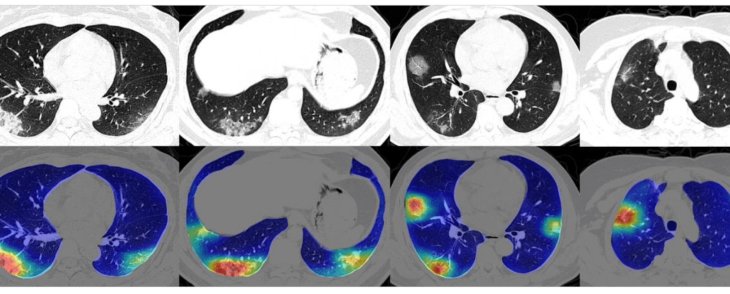

The doctors then performed an X-Ray test on him. And once they saw the report, they sensed that there was something wrong. They then decided to carry out a CT scan, which proved decisive in the recovery of Lockwood. He became India’s first COVID-19 patient to undergo a CT scan.